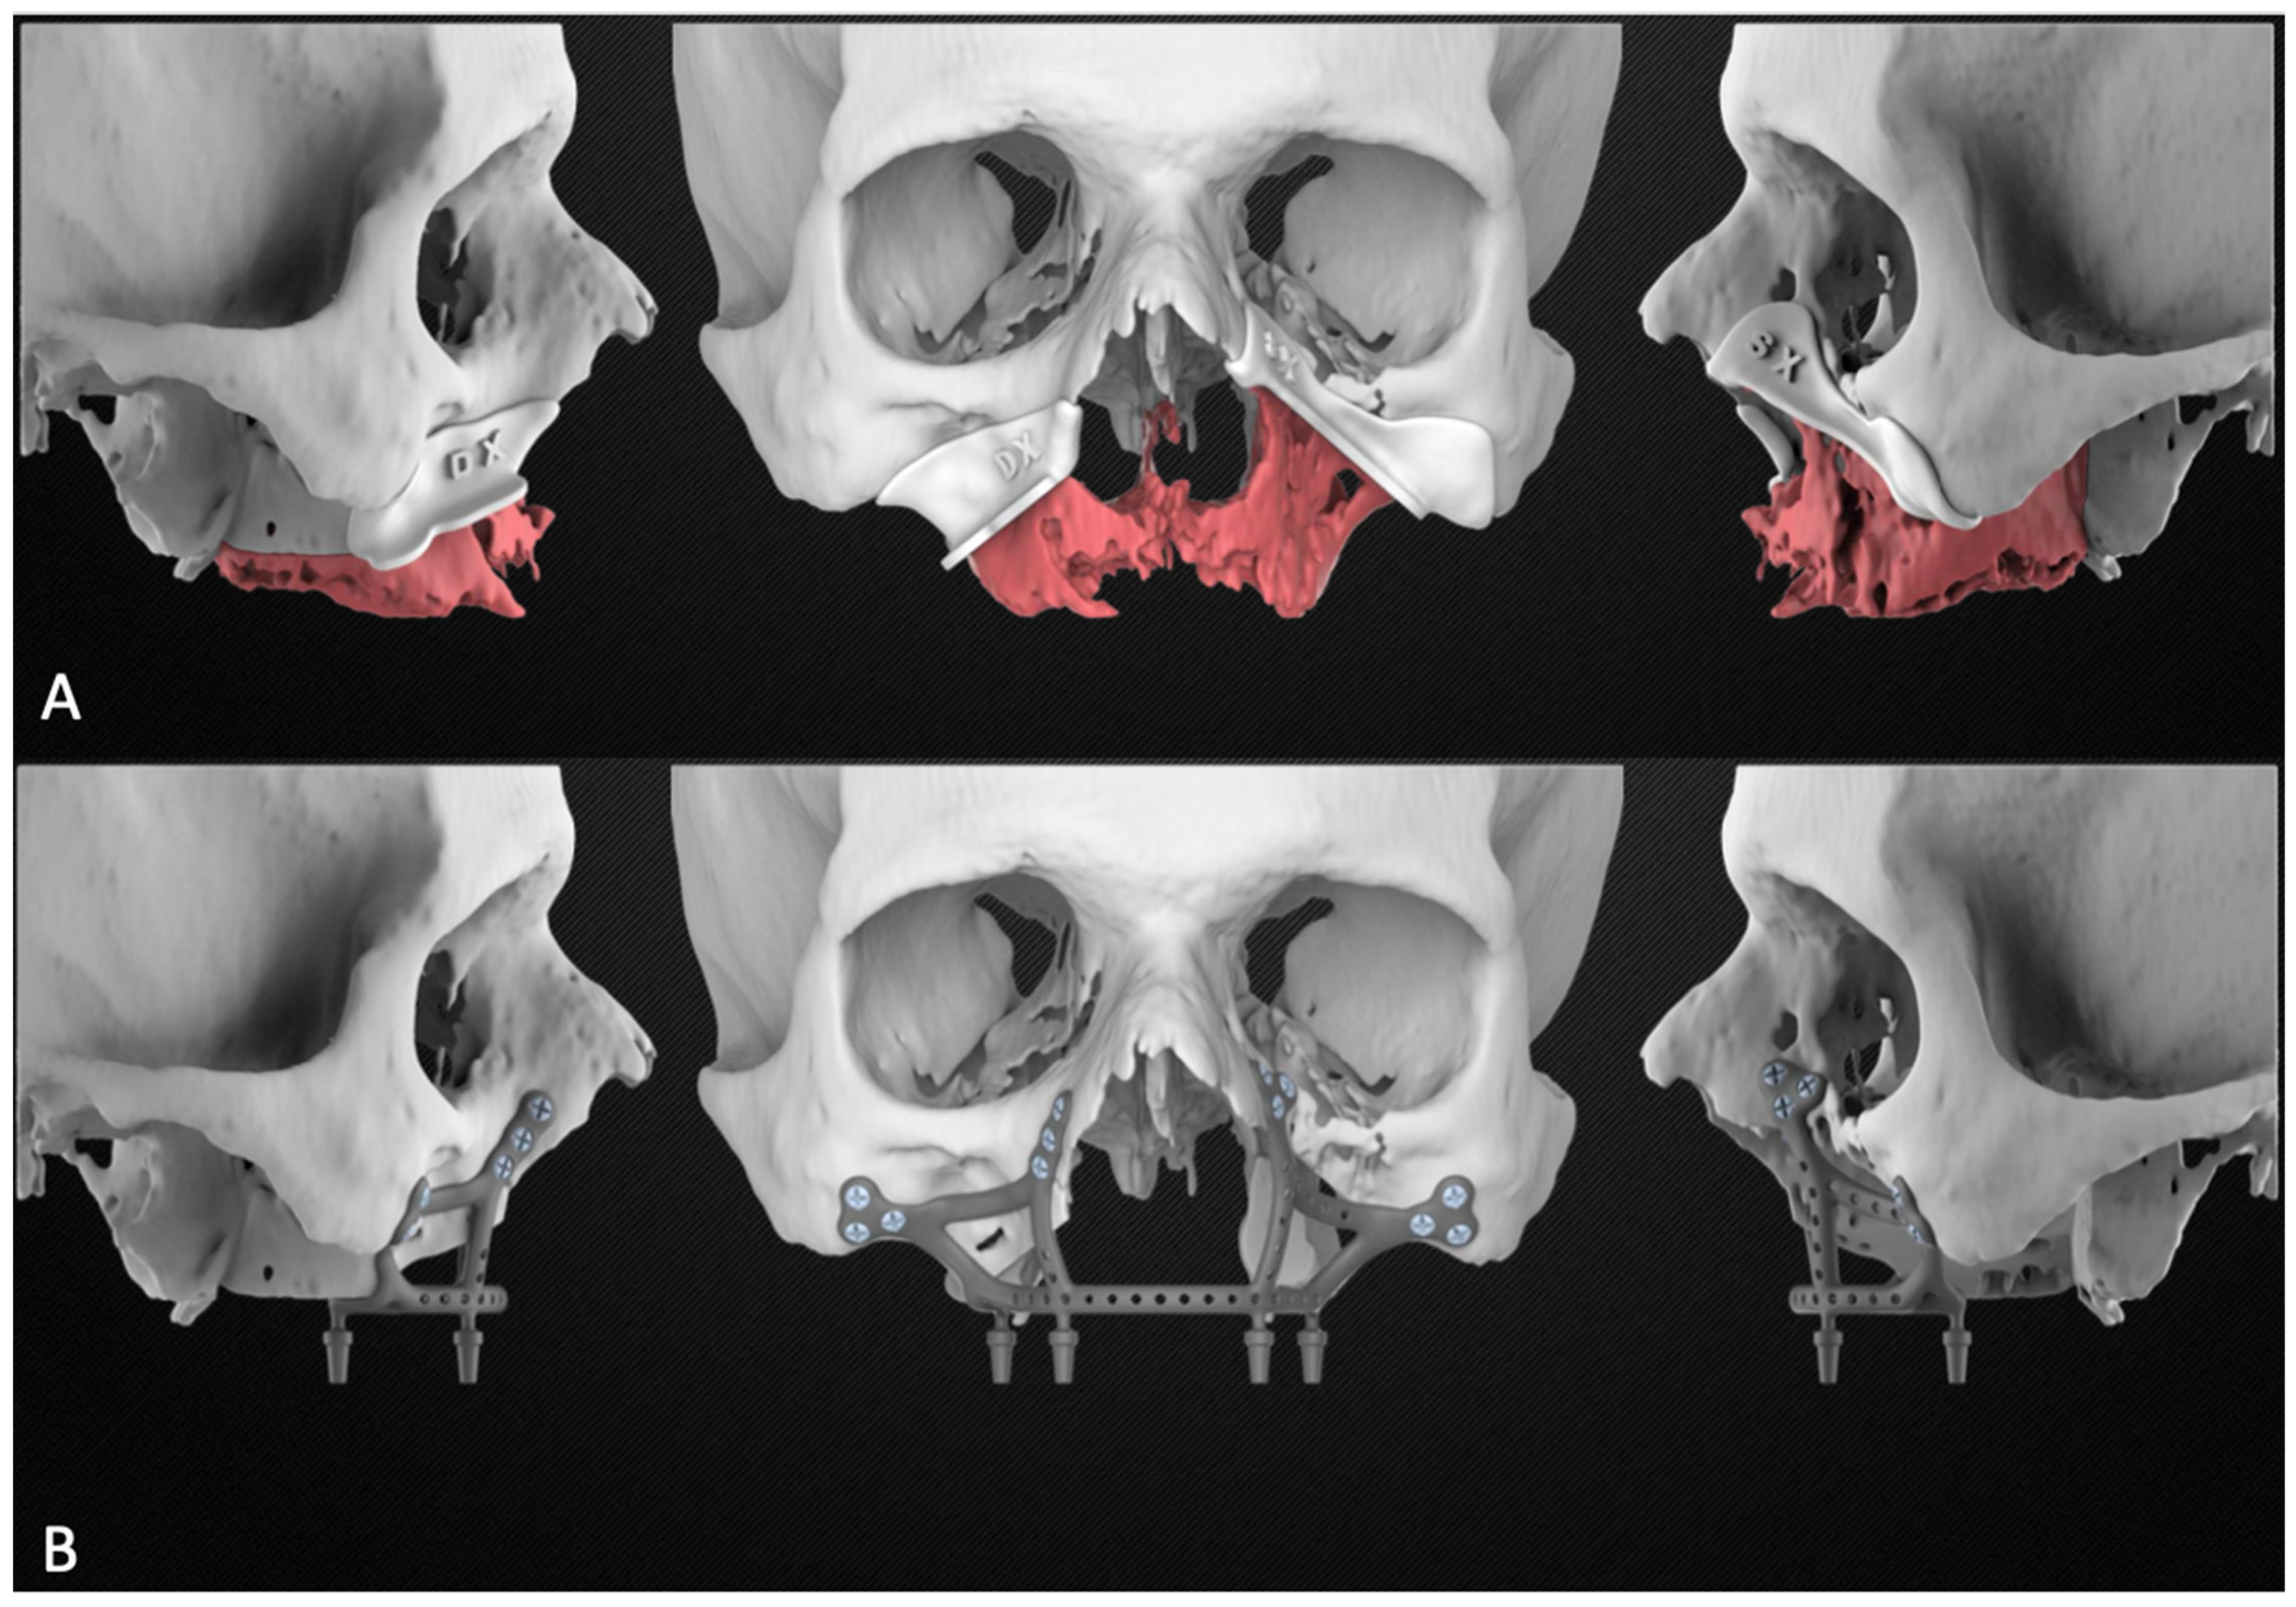

Based on the plan, the engineer then proceeded to design the subperiosteal implant and the bone resection templates. The planning report was finally sent to the surgeons for approval [Figure 3].

Figure 3.

Planning report including the maxillary resection with the cutting guides (A) and the subperiosteal implant design (B).

In this report, the possibility of performing a primary reconstruction with subperiosteal implants and local flaps is described in patients who cannot undergo reconstructions with bone flaps. In the design of the implant, some critical points must be considered. First, the bone resection must be carefully planned through an assessment of pre-operative investigations, ensuring radical excision of the tumor. If this does not happen, the extent of the bone resection may be necessary during the operation, rendering the cutting templates useless, and risking the loss of the implant’s anchoring points. For this reason, it is essential to maintain a safe distance between the most inferior screw holes and the planned osteotomy margin to allow for a correct rigid fixation, even if it is necessary to widen the demolition. Secondly, the arms of the implant are the site of maximum stress during chewing and, therefore, need to be particularly thick and reinforced [32]. In accordance with the results reported for maxillary reconstructions with load-bearing plates [37], the subperiosteal implant was designed with 2.8 mm thick arms. Thirdly, when planning the location and orientation of the screw holes, consideration should be given to which surgical approach will be performed and at what angle it will be possible to insert the screws. This is especially important for the screws on the zygomatic knob which would be impossible to insert if the holes were placed on the lateral aspect of the cheekbone and not on the anterior aspect [Figure 3]. In this position it is also feasible to exploit the major axis of the cheekbone and to insert longer screws, which ensure better stability of the implant [18,21].